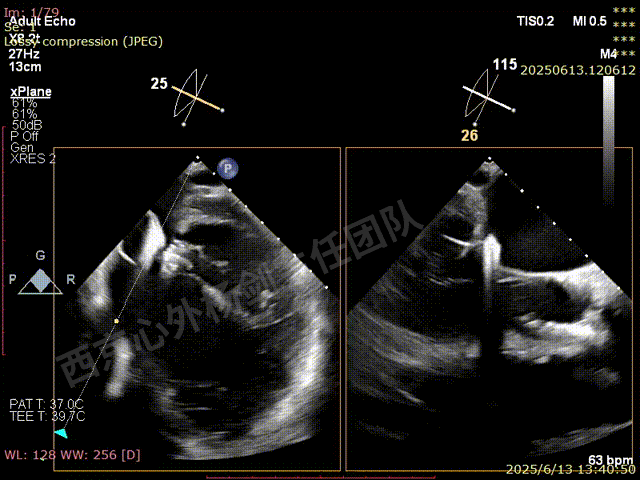

TAVR术后,全心增大,二尖瓣反流重度,三尖瓣反流重度。中量心包积液。左室严重增大,标准图像调整困难。主动脉瓣位带支架人工瓣膜瓣叶启闭正常,主动脉瓣位人工瓣上血流速度Vmax 148cm/s,PGmax 9mmHg,Vmean 86cm/s,PGmean 2mmHg, VTI 34.7cm,瓣周反流(轻)。估测肺动脉收缩压约49mmHg;左室收缩功能明显减低。LVEF:23%,EDV:364ml,ESV:221ml。

二尖瓣后叶栓系严重,前叶相对错位,反流束沿2区分布广泛,2偏3区处存在反流。

反流宽度至少23mm,因影像调整困难,考虑实际反流更宽。

1、心脏过大,术中影像标准切面难以获取,TEE引导难度较大。